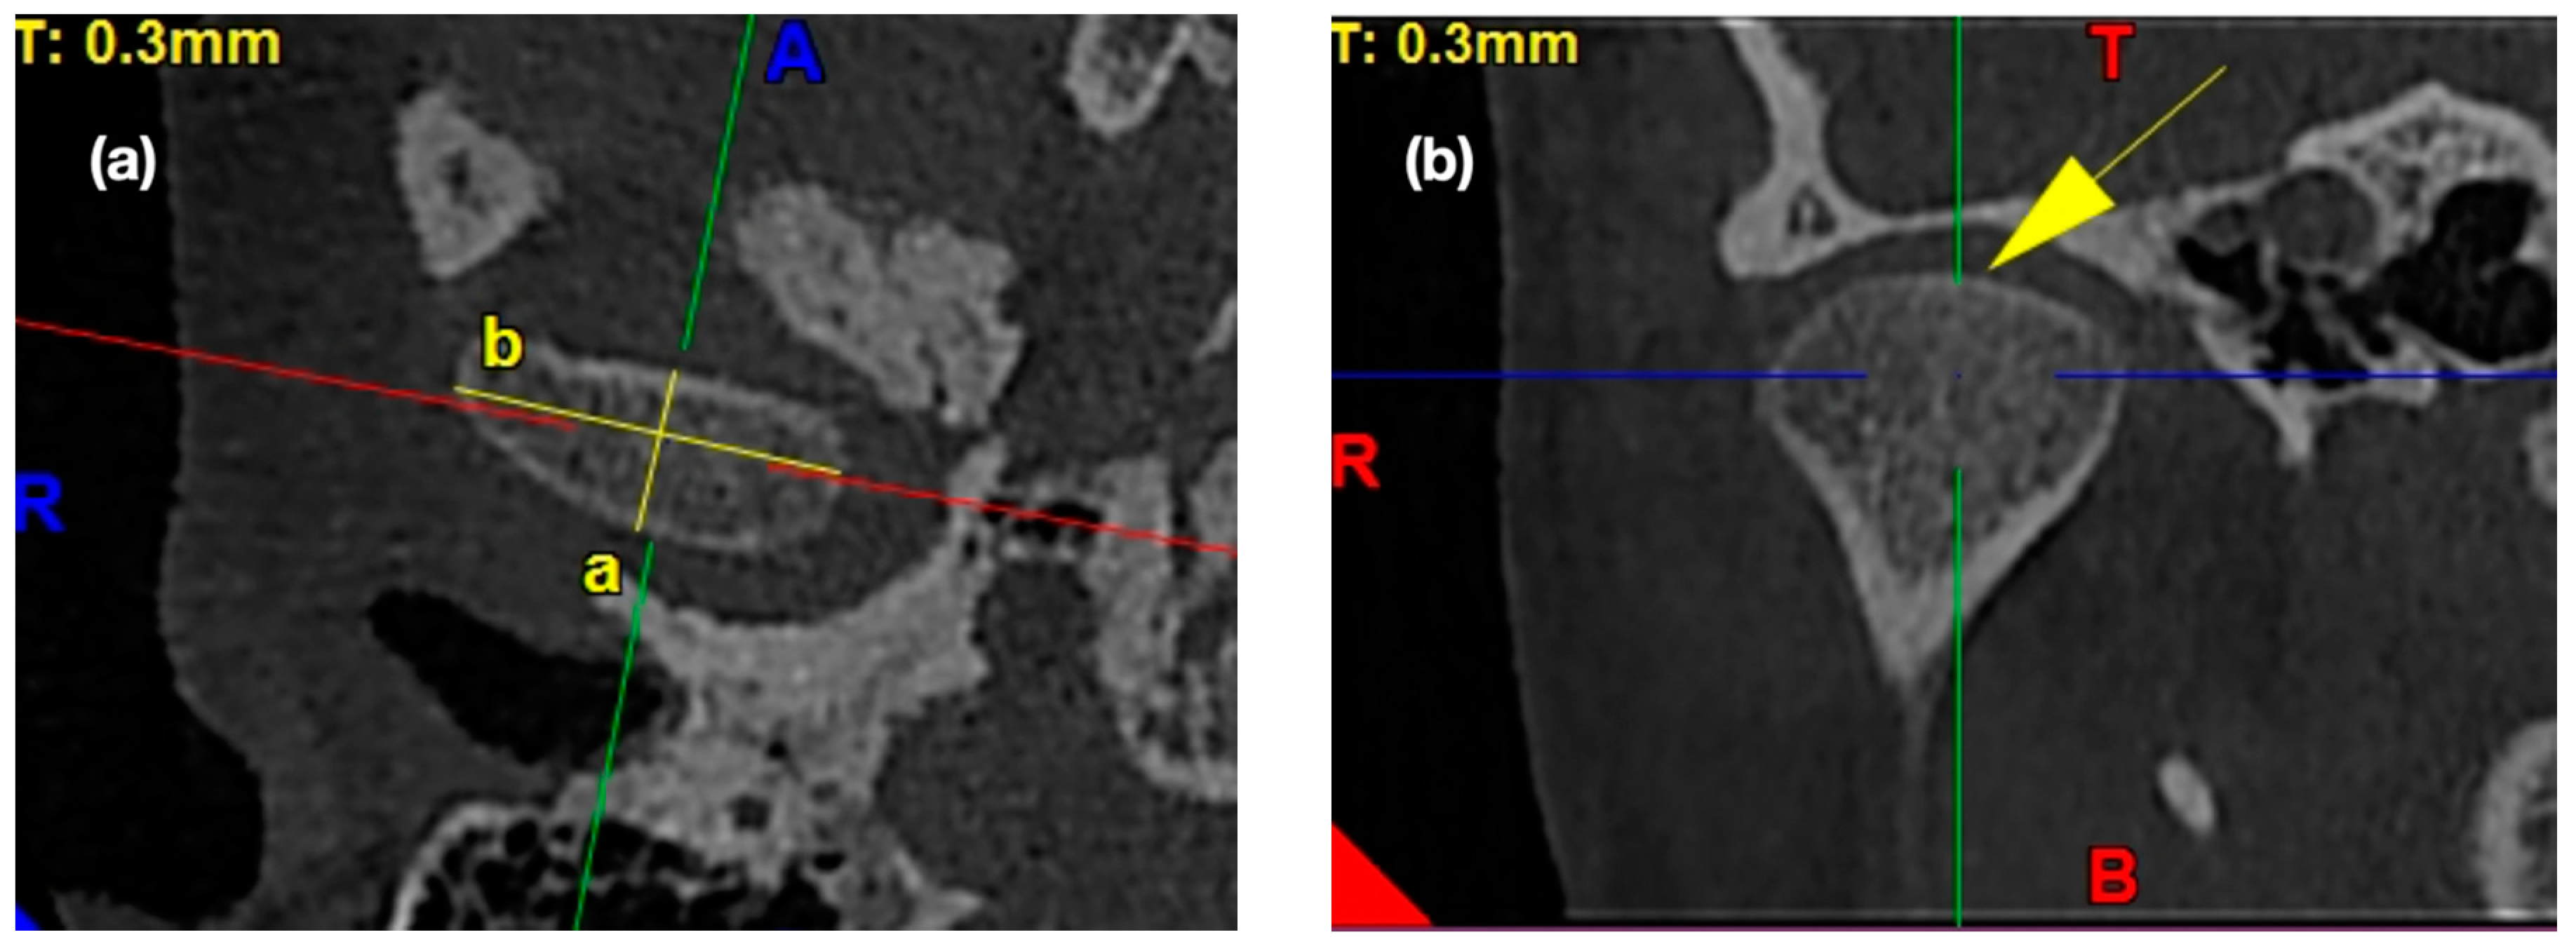

2.4.1. Morphology of the Mandibular Condyle

2.4.2. Morphology of the Glenoid Fossa (Mandibular Fossa, Articular Fossa)

2.4.3. Morphology of the Articular Eminence

2.4.4. Assessment of the Anterior, Posterior, and Superior Joint Spaces

2.4.5. Assessment of the Sagittal Position of the Condyle